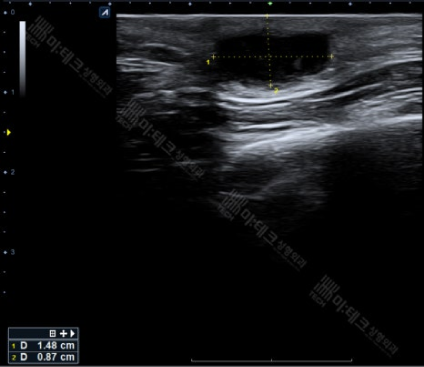

1.5cm 가량의 덩어리가 비교적 경계가 명확하게 위치하고 있습니다.